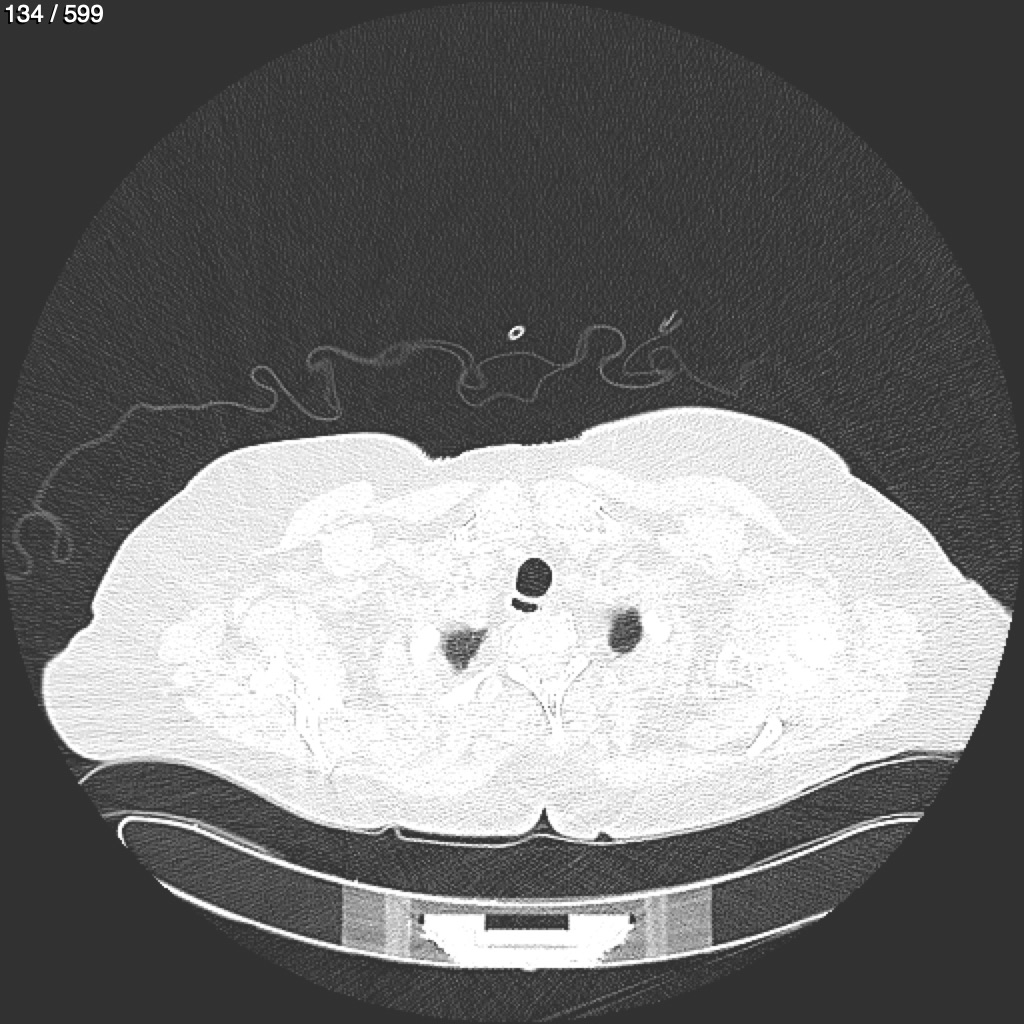

Home G​l​o​r​i​a​ ​G​l​a​d​y​s​ ​B​e​a​s​l​e​y​ ​-​ ​T​ó​r​a​x​ ​T​o​r​a​x​_​S​i​m​p​l​e​ ​(​A​d​u​l​t​o​)